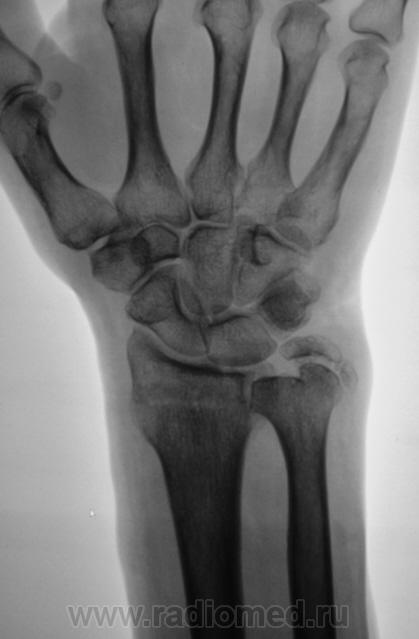

Пациент направлен на рентгенографию лучезапястного сустава.

Пациент направлен на рентгенографию лучезапястного сустава хирургом, была травма. После производства снимков стали допытываться у пациента, о "факте более ранней травмы". Все бесполезно - не помнит, не знает ....

Ваше мнение, уважаемые коллеги?

А линия просветления в метаэпифизе луча?

Контур нечеткий, склероз и т.д.-на перелом не схоже. А действительно локальная болезненность в латер. лодыжке?

Да, болезненность есть, клинически хирурги - за перелом.

Краевой перелом Наружной лодыжки